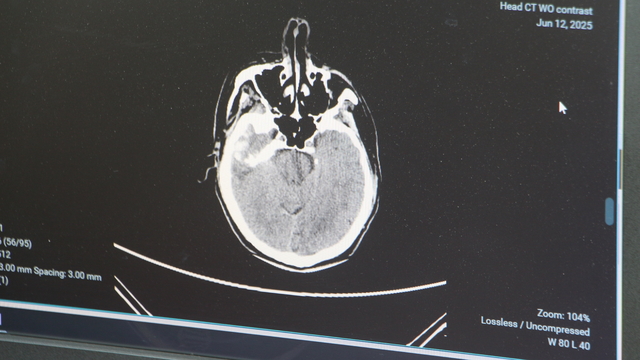

ADANA Şehir Hastanesi Beyin ve Sinir Cerrahisi Bölümü'nden Doç. Dr. Ali İhsan Ökten, 100 binde 10- 15 kişide görülen ve daha çok 50 yaş üzerindeki hastalarda rastlanan beyin kanamalarının hızlı yaşam tarzı, stres ve yanlış beslenme kaynaklı tansiyon yükselmelerine bağlı olarak gençlerde daha sık görülmeye başlandığını belirtti. Ökten, “Bunun önüne geçebilmek için özellikle gençlere sıkıntılı ve stresli ortamlardan uzak durmalarını tavsiye ediyorum” dedi.

Genellikle 50 yaştan sonra görülen beyin kanaması, son yıllarda gençlerde daha sık görülmeye başlandı. Sebeplerine dikkati çeken Adana Şehir Hastanesi Beyin ve Sinir Cerrahisi Bölümü’nden Doç. Dr. Ali İhsan Ökten, bunların daha çok ‘arteriyovenöz malformasyon’ ve ‘anevrizma’ kaynaklı yaşandığını söyledi. Anevrizma, yani kan damarlarının duvarında oluşan baloncuk şeklindeki patolojik genişlemeler kaynaklı yaşanan beyin kanamalarının 100 binde 10 ile 15 kişi arasında görüldüğünü dile getiren Doç. Dr. Ali İhsan Ökten, “Gençlerde görülme oranı giderek artıyor” dedi.